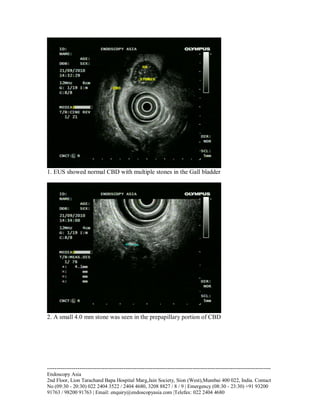

1. EUS showed normal CBD with multiple stones in the Gall bladder

2. A small 4.0 mm stone was seen in the prepapillary portion of CBD